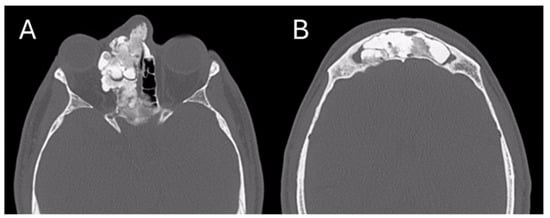

The patient had already performed a skull CT scan that showed an osteostructural alteration with a swollen appearance of the bone component of the right ethmoidal cells, with the encumbrance of the homolateral nasal fossa and the probable involvement also of the homolateral orbital walls; the neoformation was 24 × 43 × 38 mm (Figure 1).

Figure 1. Pre-operative CT Image of Patient 1. (A) An axial cut; (B) a coronal cut. In both, the extension of the lesion into the ethmoidal region is evident.